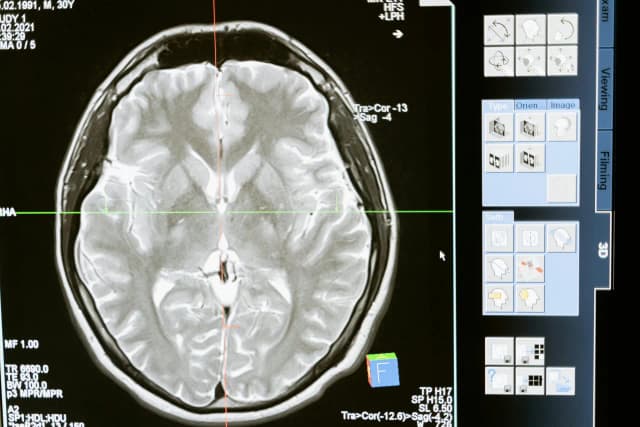

Tag jak pomóc osobie z udarem